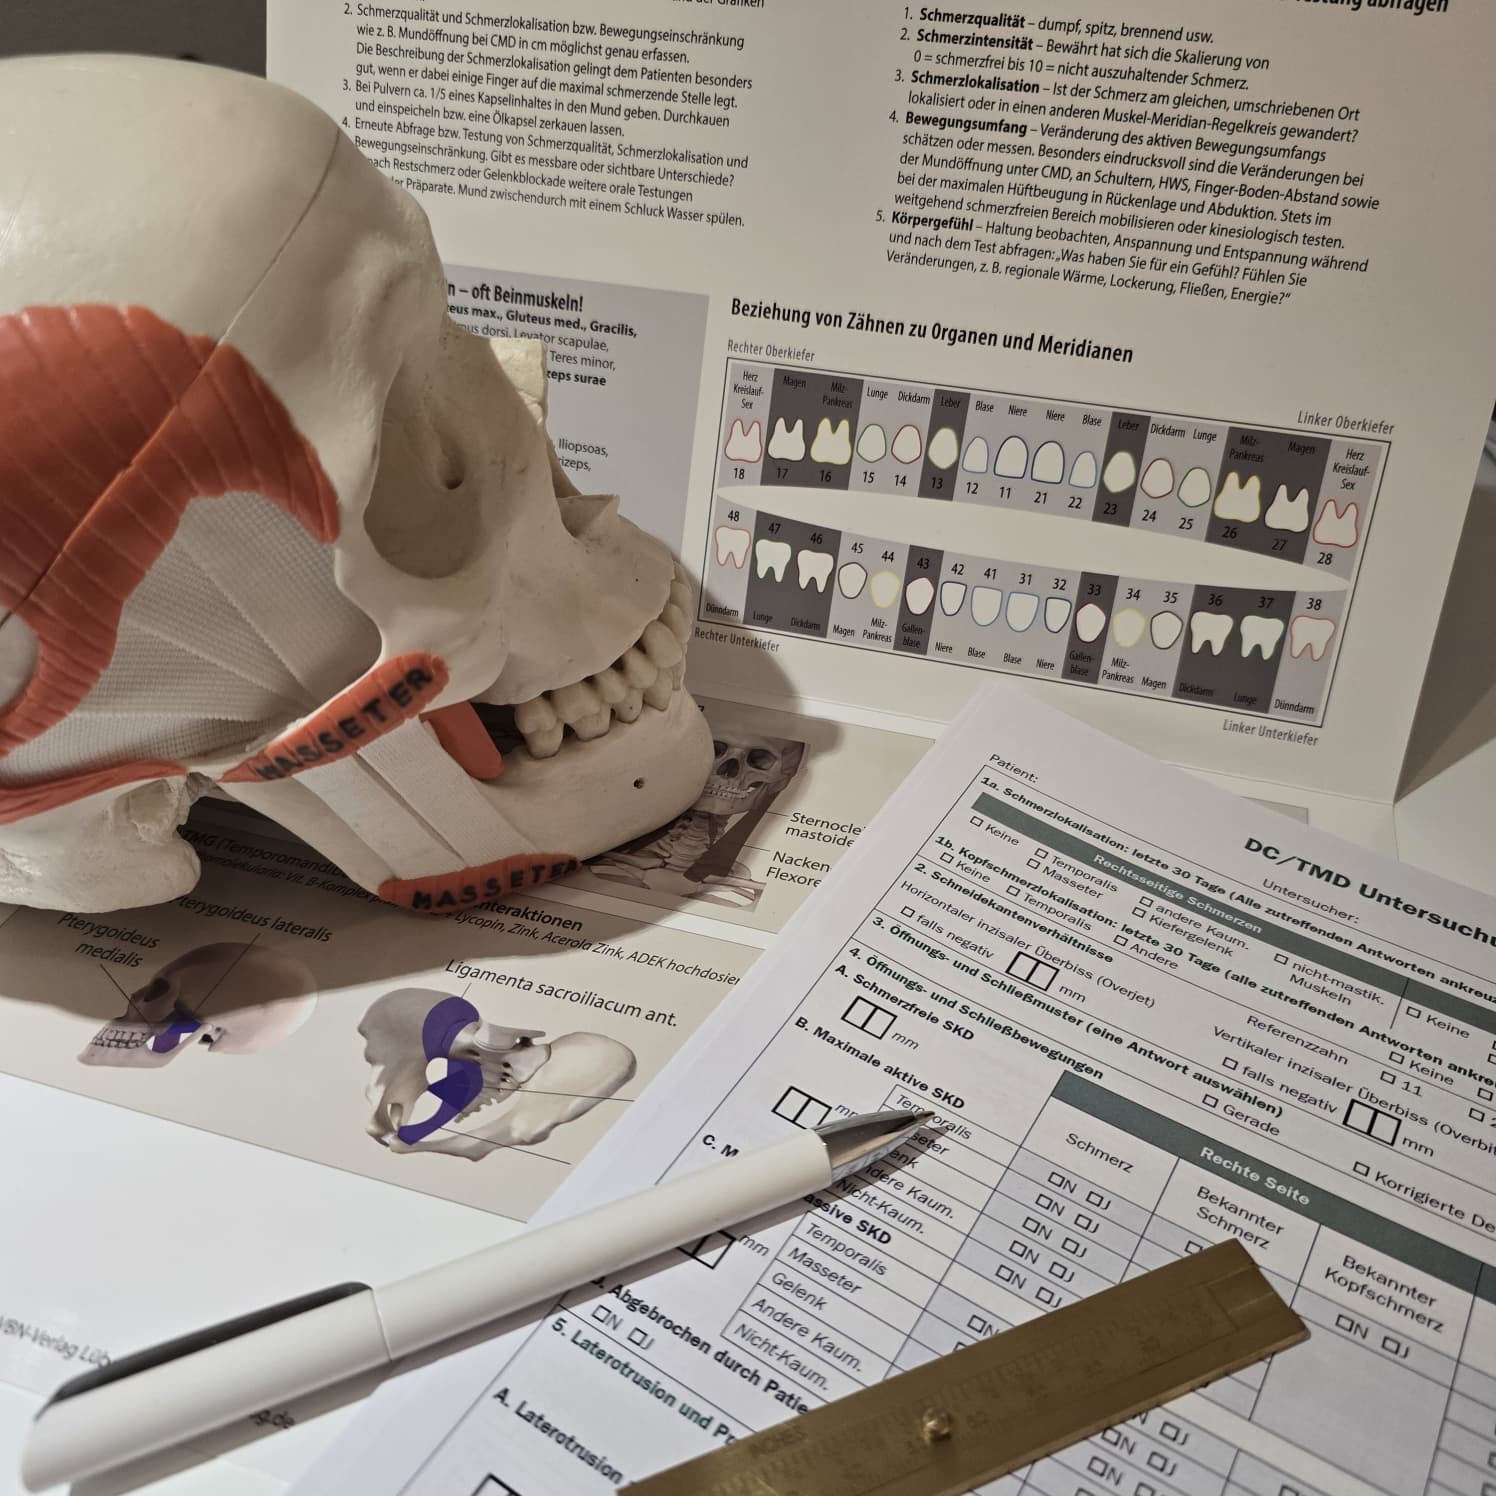

Der Begriff „Craniomandibuläre Dysfunktion (CMD)“ beschreibt einen Sammelbegriff für strukturelle, funktionelle, biochemische und psychische Fehlregulationen der Muskel- und Gelenkfunktionen von Ober- und Unterkiefer.

Ziel der CMD-Behandlung ist es, die Muskulatur zu entspannen, funktionelle Störungen auszugleichen und Schmerzen zu reduzieren.

Wir analysieren Ihr Kausystem und Ihren Zahnstatus, um gesundheitliche Risiken frühzeitig zu erkennen.

Die ganzheitliche Beurteilung von Panoramaaufnahmen (OPG) ermöglicht einen vernetzten Blick auf die Mundgesundheit – nicht nur auf einzelne Zähne, sondern auf die Zusammenhänge zwischen Zahn-Kiefer-Funktion, Immunsystem und Regulationsfähigkeit des gesamten Organismus.

Im Rahmen der Odonto-Systemik analysieren wir Ihr Kausystem, um gesundheitliche Risiken frühzeitig zu erkennen. Dabei betrachten wir auch, welche Auswirkungen Erkrankungen der Zähne, des Mundraums und des Kiefers auf den restlichen Körper sowie auf die psychische Gesundheit haben können. Dies erfolgt in enger Zusammenarbeit mit Zahnärzten und Zahnärztinnen, um eine umfassende und fachübergreifende Betrachtung zu gewährleisten.

Zur Diagnostik nutzen wir unter anderem:

Im Rahmen meiner ganzheitlichen Praxis nutze ich die kinesiologische Austestung als biofunktionelles Feedback-System, um neuro-fokale Störfelder sowie biologische Interaktionen im Kopf- und Zahnbereich zu identifizieren, die über die rein strukturelle Diagnostik hinaus den Gesamtorganismus belasten können.